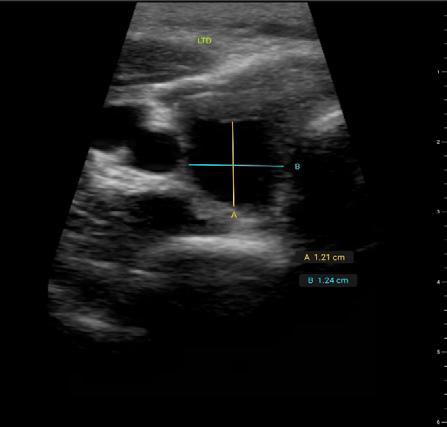

Issuu converts static files into: digital portfolios, online yearbooks, online catalogs, digital photo albums and more. Sign up and create your flipbook.